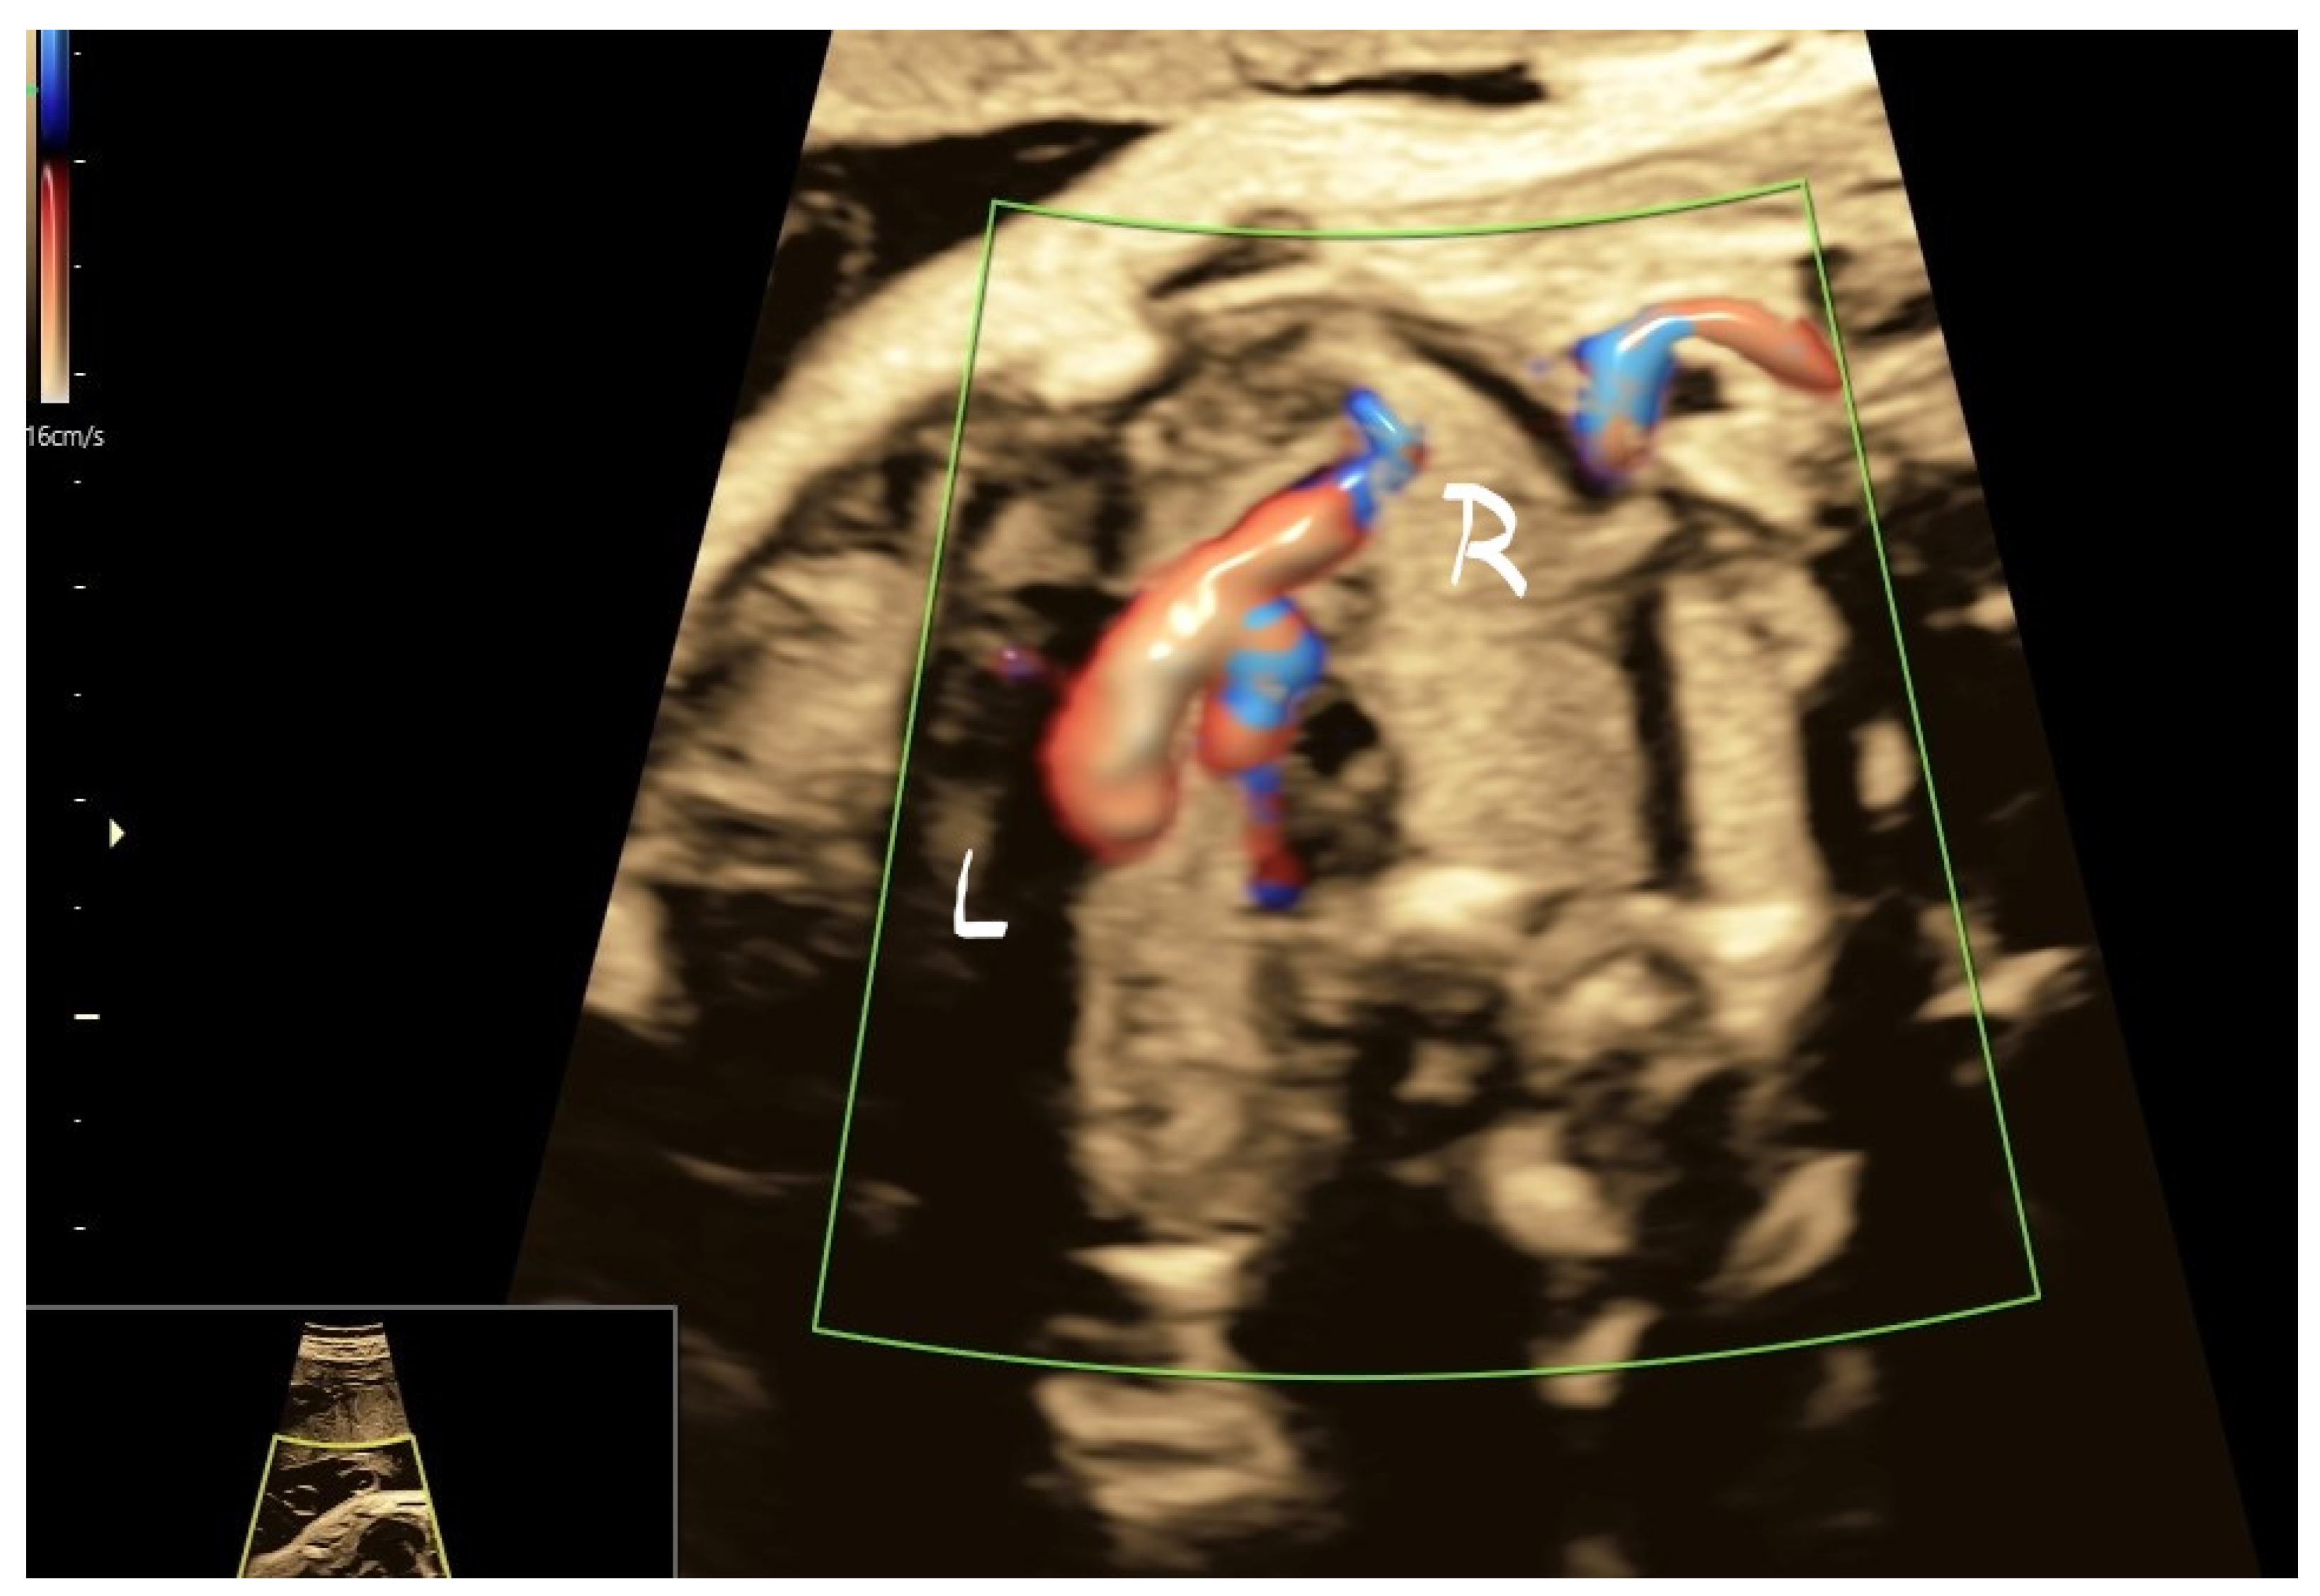

4.2. Case 2